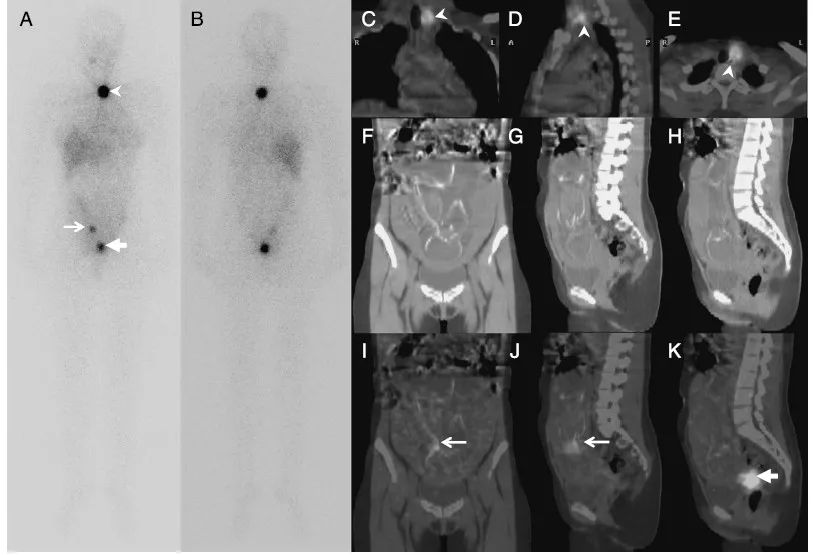

[以下内容翻译为百度机器翻译,仅供参考]Anterior and posterior views(A and B) of whole-body scan after 131I treatment; coronal, sagittal, and axialCT images (FYH for abdomen) and SPECT/CT (CYE for chest and FYH for abdomen). 【131I治疗后全身扫描前后视图(A和B);冠状面、矢状面和轴向CT图像(腹部为FYH)和SPECT/CT(胸部为CYE,腹部为FYH)。】A 25-year-old woman came toour department with a diagnosis of papillary thyroid carcinoma after totalthyroidectomy for 131I treatment. The procedure proceeded with unremarkable pregnancystatus. The patient who is a mother of 2 reported to be on contraceptive pillswith monthly period, and the urine pregnancy test result was negative. 【一位25岁的女性在接受131I甲状腺全切除术后,被诊断为甲状腺乳头状癌。手术过程中,孕妇的情况并不显著。该患者为2个孩子的母亲,每月服用避孕药,尿检结果为阴性。】On post 131I treatmentimaging, there is a usual residual thyroid activity at the left thyroidectomybed (white arrowheads). On whole-body scan, there are additional 2 iodine-avidfocal lesions (white arrows) in the abdominopelvic region, which are possiblefor bone metastases involving the pelvic bony structures. (1,2)Other possibilities include physiologiciodine distribution or variant in the gastrointestinal and genitourinarytracts.(3-8) SPECT/CT is a helpful technique for additional localization.【在131I治疗后的影像学检查中,左侧甲状腺切除床(白色箭头)有残留的甲状腺组织。在全身扫描中,在盆腔有2个额外的摄碘病灶(白色箭头),可能发生骨转移,累及骨盆骨结构 (1、2) 其他的可能性包括生理上的碘分布或在胃肠道和泌尿生殖道的变异 (3-8) SPECT/CT是一种有助于进一步定位的技术。】In our case, the moreinferior focus is in the uterine cervical region on SPECT/CT (K, thicker whitearrow), which could be nabothian cyst,(3,4) a common finding especially in woman with multiplepregnancies. 【在我们的病例中,SPECT/CT (K,粗大的白色箭头)下位病灶多位于子宫颈区域,可能是纳博特囊肿(3,4),这是多胎妊娠妇女的常见表现。】The other, a more superior focus,corresponds to the location of the fetal thyroid gland (IYJ, thinner whitearrows), which concentrates iodine or functions after the first trimester.(9)【另外一个浓聚点,与胎儿甲状腺的位置相对应(IYJ,较细的白色箭头),它在妊娠早期浓缩碘或起作用(9)】Unexpectedly, the patient hadbeen pregnant for about 20 weeks of gestational age with monthly vaginal spottingand negative urine pregnancy test result before the treatment. The serumpregnancy test may be more sufficient in detecting pregnancy. However, thevaginal spotting and false-negative pregnancy tests, either urine or serumsamples, have been previously reported with pregnancy(10,11).【出乎意料的是,患者在治疗前已怀孕约20周,每月阴道点滴出血,尿检阴性。血清妊娠试验对妊娠的检测可能更充分。然而,阴道点滴出血和假阴性妊娠试验,无论是尿液还是血清样本,在怀孕之前都有报道(10,11)】The patient had no currentdesire for more children; therefore, she subsequently had an abortion. Thiscase emphasizes the helpfulness of SPECT/CT in the localization or diagnosis ofiodine-avid focus within the abdomen and confirms the function of the fetalthyroid gland beyond the first trimester of gestation.【病人目前没有要更多孩子的愿望;因此,她后来堕胎了。本病例强调SPECT/CT对腹部摄碘病灶定位或诊断的帮助,并确认胎儿甲状腺在妊娠早期的功能。】